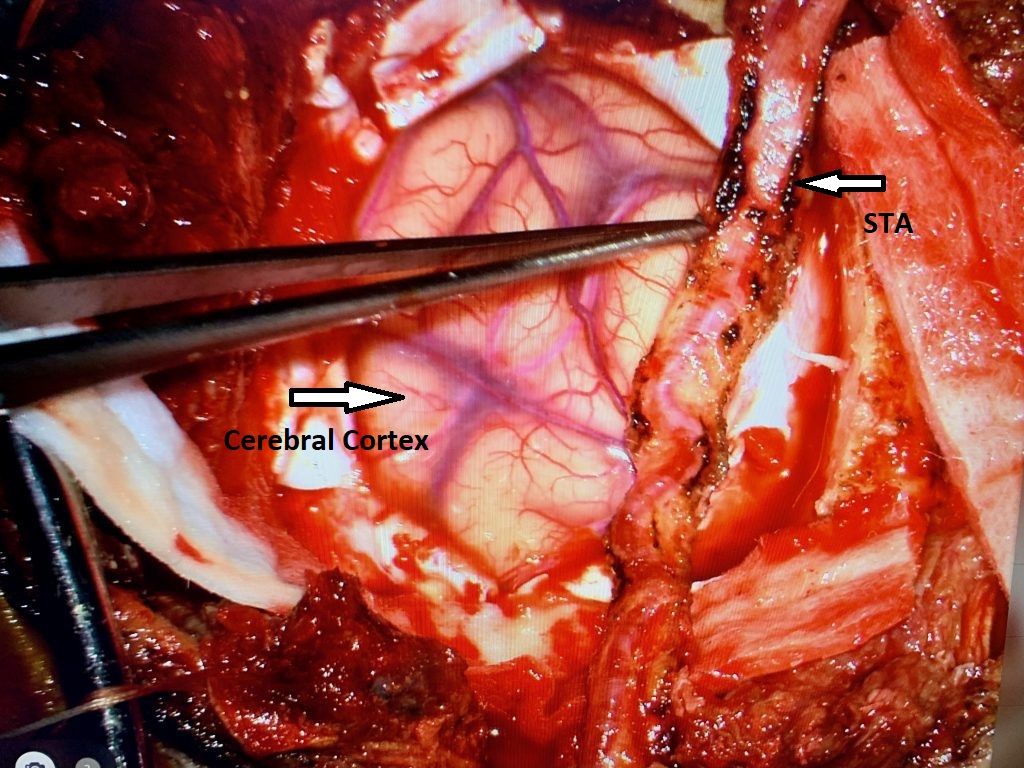

Brain:

Neurosurgeons Collaborate to Treat Giant Symptomatic Meningioma

Author: Ramin Rak M.D., F.A.A.N.S., F.C.N.S., Jonathan L. Brisman M.D., F.A.C.S., Read More!

Pineal Region Meningioma

Author: Michael Brisman M.D., F.A.C.S., Read More!

Atypical Convexity Meningioma

Author: Jonathan L. Brisman M.D., F.A.C.S., Read More!